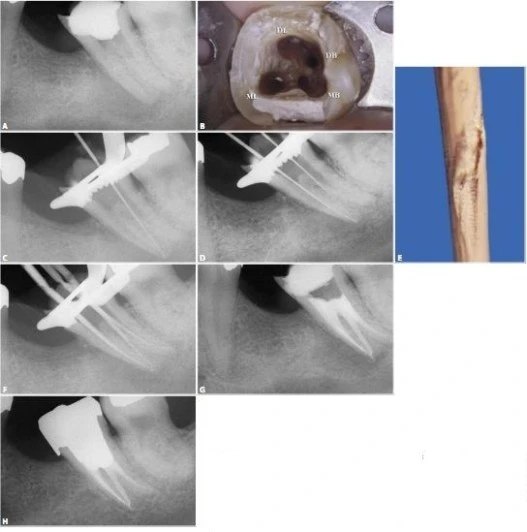

Hình 11.112. Trong một số trường hợp khác, ống tủy gần giữa được thấy ở 1/3 chóp của chân gần.

Hình 11.113. Điều trị lại R46 vì điều trị sót 2 ống tủy: ống xa ngoài và ống gần giữa. A. Phim trước điều trị. B. Xoang tủy sau khi bộc lộ 4 ống tủy. Chú ý sự hiện diện của 1 chỗ lõm ở vùng eo giữa 2 chân gần. C. Một file số 10 đi vào chỗ lõm và  rất dễ dàng đi vào ống tủy gần giữa, ống này có một lỗ chóp riêng. D. Xoang tủy sau khi sửa soạn 5 ống tủy E. Ba file chỉ ra rằng có 3 ống tủy riêng biệt ở chân gần  F. Phim sau điều trị. G. Một góc chụp khác cho thấy hình ảnh 5 ống tủy. H. 7 năm sau điều trị, tổn thương lành hoàn toàn.

Thương tổn trước đây không phải do vật liệu trám ra ngoài mà vì vi khuẩn còn lại trong ống tủy bị bỏ sót.